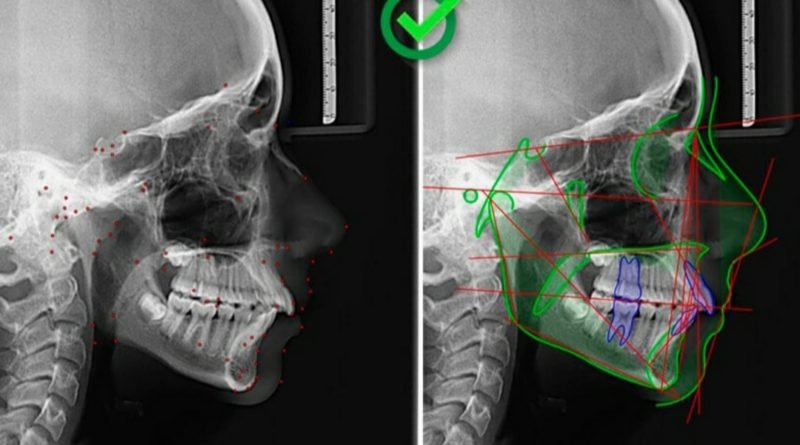

O Studio 3 é um software que pode ser aberto tanto em dispositivos móveis quanto em desktop. Este sistema criado pela Radio Memory é feito para armazenar imagens de exames radiológicos sem que o usuário necessite de um equipamento robusto. Com constante aperfeiçoamento, o mais novo recurso é o uso de inteligência artificial (IA) para realização de análises cefalométricas (craniofaciais), de modelo e de cervical (exames laterais, frontais, faciais e estudos de modelos), batizado de CEFBOT, com tecnologia 100 % nacional. Antes, esses exames eram realizados manualmente em computadores, um trabalho que levava cerca de 10 minutos. Agora, tanto o radiologista como o dentista possuem acesso e resultado dessa medição instantaneamente, feita por IA. O sistema oferece total segurança dos dados e conformidade com a nova LGPD, além de possuir registro na ANVISA.